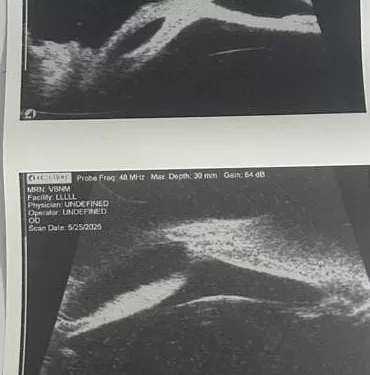

أعلن الدكتور حمودة الجزار، وكيل وزارة الصحة بالدقهلية، عن تشغيل جهاز UBM (Ultrasound Biomicroscopy) في مستشفى رمد المنصورة، مؤكدًا أن هذا الجهاز يمثل نقلة نوعية في مجال التشخيص الدقيق لأمراض العيون، ما يسهم في الارتقاء بجودة الخدمات الطبية المقدمة للمرضى.

وأوضح وكيل الوزارة أن الجهاز يُمكّن الأطباء من فحص وتشخيص أدق تفاصيل العين، والتعرف على أورام العين الأمامية، وتقييم حالات المياه الزرقاء (الجلوكوما)، وتشخيص الأمراض الناتجة عن النمو غير المكتمل للمنطقة الأمامية للعين، بالإضافة إلى إجراء الفحوصات اللازمة قبل زراعة القرنية. وأكد أن هذه الخطوة تأتي في إطار حرص مديرية الصحة على توفير أحدث التقنيات لخدمة أهالي الدقهلية والمحافظات المجاورة.